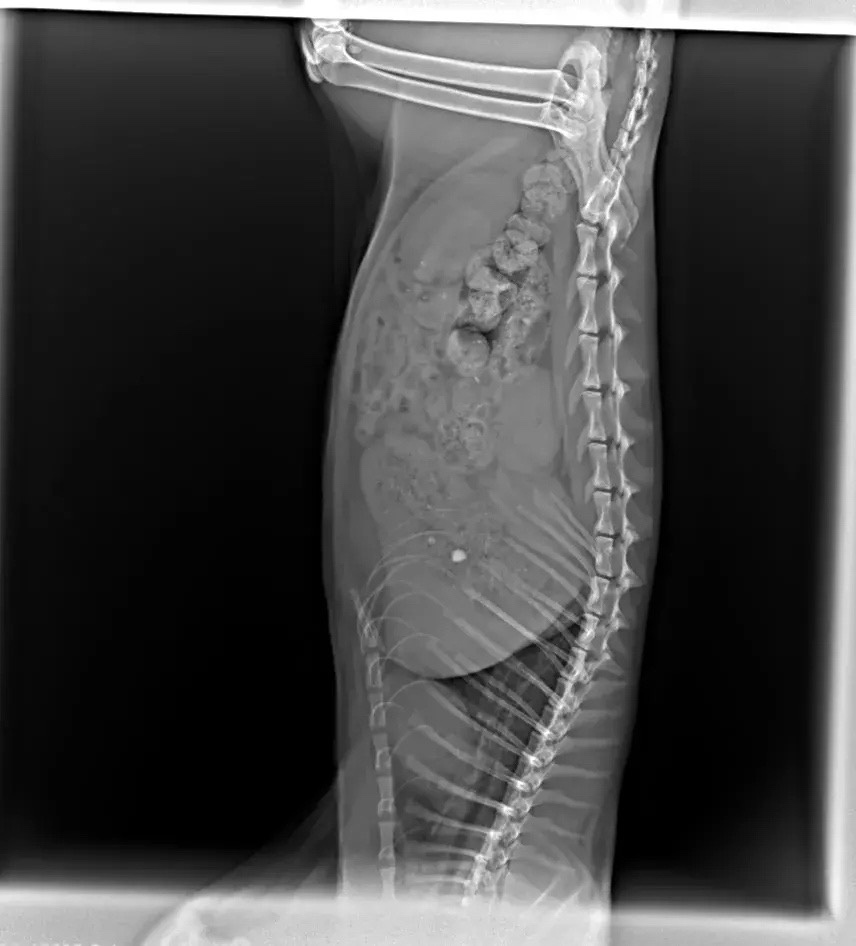

Это ещё не всё. Поступил новый разодранный котик, в запущенном состоянии совсем. Лапа разодрана, болит, кровоточит. Самое главное, что мы сделали РЕНТГЕН и у котика какашки стоят колом, клизма НЕ помогает, нужно оперировать, а это снова деньги. До операции нужно СДАТЬ АНАЛИЗЫ, ни один адекватный врач не возьмётся оперировать животное, о состоянии которой ничего не известно. Любая операция - ЭТО НАРКОЗ! Огромные риски…. а ведь мы же все таки хотим СПАСТИ, а не угробить…